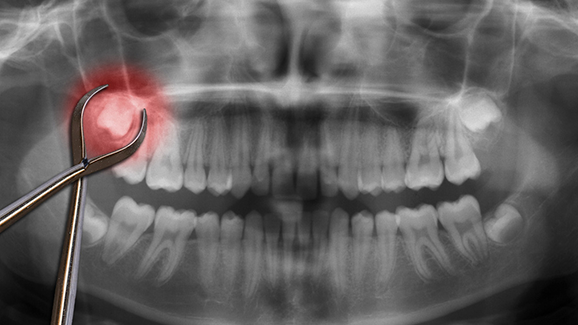

LEIPZIG – Auch wenn eine Weisheitszahn-OP heute zum Alltag eines Kieferchirurgen gehört und kaum noch Komplikationen auftreten, ist jede Operation immer mit einem gewissen Risiko verbunden. Sollte man dieses eingehen, auch wenn besagte Zähne dem Patienten keinerlei Probleme bereiten? Bisher konnte keine wissenschaftlich signifikante Studie dies nachweisen.

Die größten Risiken bei der Entfernung von Weisheitszähnen sind Infektionen, Entzündungen oder sogar kurzweilige Nervenverletzungen. Auch wenn eine OP mittlerweile Routine für den zuständigen Facharzt ist, sollte man die möglichen Gefahren stets im Hinterkopf behalten. Andererseits können Komplikationen auch noch im höheren Alter auftreten, und dann eine Operation durchzuführen, verstärkt diese Risiken zusätzlich. Hossein Ghaeminia, Mitarbeiter der Radboud Universität, empfiehlt aufgrund der fehlenden wissenschaftlichen Beweise für ein Für und Wider der präventiven Weisheitszahnentfernung deshalb immer eine individuelle Beratung beim zuständigen Kieferchirurgen.